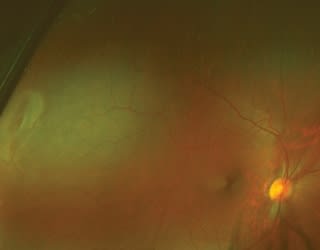

| Case 1 Patient history: A 20-year-old Caucasian man reporting no health problems, symptoms or visual complaints had a routine eye exam in April 2005.

The Optomap Retinal Exam shows a new retinal hole (reddish oval, far right) at the 9 o'clock position in the right eye, just posterior to the ora serrata. Clinical summary: The patient chose to have an Optomap Retinal Exam that appeared to reveal two small retinal holes at approximately 8 o'clock in the right eye just posterior to the ora serrata. Because of this finding, I performed a dilated fundus exam (DFE) with scleral depression, confirming the diagnosis of two atrophic retinal holes in that location with no surrounding fluid cuff.I referred him to a retinal specialist who confirmed the diagnosis. Because the patient had no symptoms, there was no fluid cuff around the holes, and prophylactic laser treatment could induce more retinal holes, we decided to carefully monitor the retina for new changes or symptoms every 6 months. At the most recent routine eye examination, the patient hadn't had any retinal changes (as observed with DFE and scleral depression) for 3 years, so we chose an Optomap Exam in lieu of dilation. Unfortunately, the new Optomap image appeared to show a previously undiagnosed atrophic retinal hole at approximately 9 o'clock just posterior to the ora serrata. Because this was a new finding, we performed a DFE, confirming an atrophic retinal hole. Prior Optos images showed that this retinal hole wasn't present in past exams. Patient outcome: This new retinal finding prompted me to refer the patient to a retinal specialist to reconsider prophylactic laser treatment for these retinal holes. We're awaiting the retinal surgeon's treatment decision. Case 2 Patient history: A 21-year-old, slightly overweight Caucasian woman with no other reported health problems had a routine eye exam for contact lenses. She said her distance vision had been decreasing gradually in both eyes over the previous year, which she attributed to a normal prescription change over time. Clinical summary: This patient chose to have an Optomap Retinal Exam just as she had done in the prior 2 years. Her best-corrected acuity was 20/20 OD and 20/20-3 OS through a moderate compound myopic astigmatic spectacle prescription. Anterior segment biomicroscopy revealed no remarkable findings. An undilated fundus exam with a superfield lens revealed slightly elevated and nondistinct optic discs in both eyes, with a cup-to-disc ratio of 0.2/0.2 in both eyes. There was a spontaneous venous pulse in both eyes. All other fundus findings were unremarkable. On previous exam charts, her optic nerves had been recorded as distinct and flat and her cup-to-disc ratio had been recorded as 0.3/0.3 in both eyes. Because of these suspected changes in the optic nerves, I needed to rule out recent onset of papillitis. I reviewed the Optomap scans from the past 2 years.